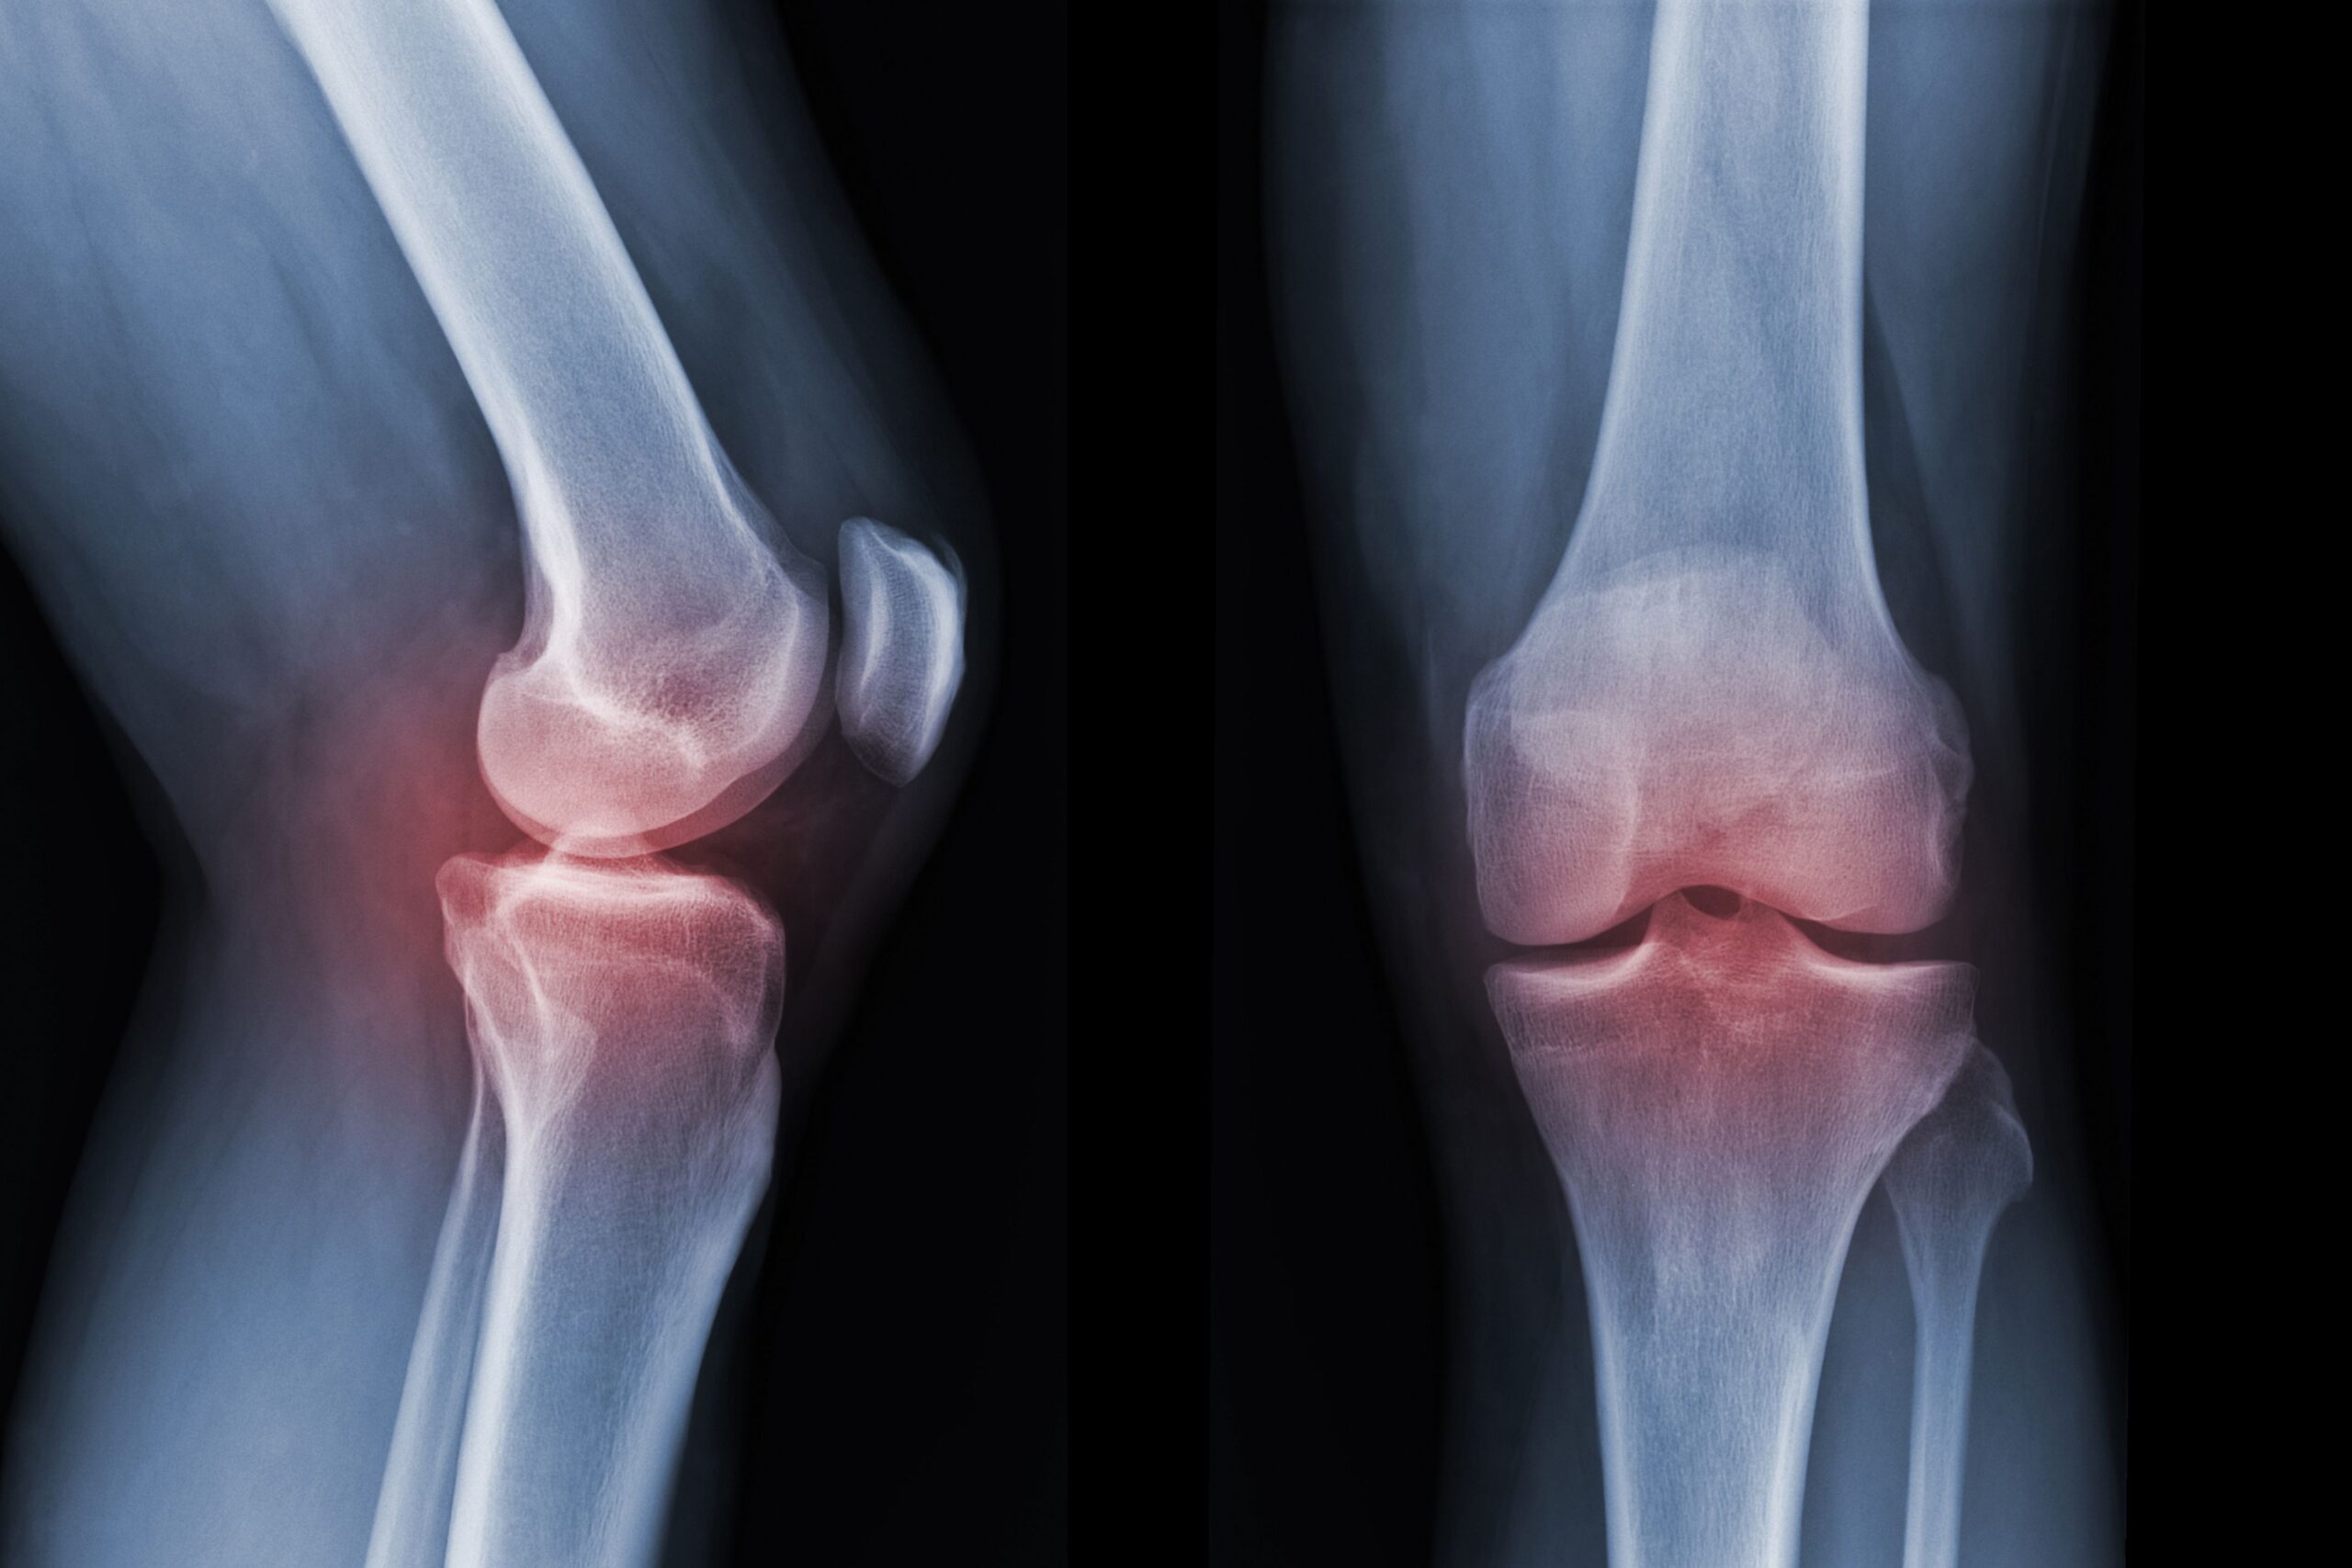

Non solo è dolorosa e profondamente debilitante: l’artrosi, patologia caratterizzata dal progressivo deterioramento delle cartilagini articolari, è purtroppo anche molto diffusa. Si stima che nel mondo comprometta la mobilità di un adulto su cinque e, in ragione dell’invecchiamento della popolazione, potrebbe diventare ancora più frequente nei prossimi anni, con un sensibile aumento dei casi – del 75% per il ginocchio, del 48% per la mano, del 70% per l’anca – entro il 2050.

Per verificare questa ipotesi, i ricercatori hanno confrontato la concentrazione di enzima nella cartilagine del ginocchio di topi giovani rispetto a esemplari anziani, riscontrando che di fatto aumentava di circa due volte con l’età. Hanno successivamente testato l’iniezione, nei topi anziani, di un farmaco capace di inibire l’attività di 15-PGDH, sia a livello sistemico che somministrandolo direttamente nell’articolazione. Quello che hanno osservato è un ispessimento localizzato della cartilagine, a conferma che il trattamento promuoveva la rigenerazione laddove deteriorata dall’invecchiamento.

Risultati simili sono stati osservati in animali giovani con artrosi post-traumatica derivante da una rottura del legamento crociato anteriore (che si verifica con una certa frequenza negli sportivi). Altri esperimenti hanno dimostrato una significativa riduzione del dolore: gli esemplari che avevano ricevuto il trattamento erano inclini a caricare più peso sulla zampa interessata rispetto a quelli non trattati.